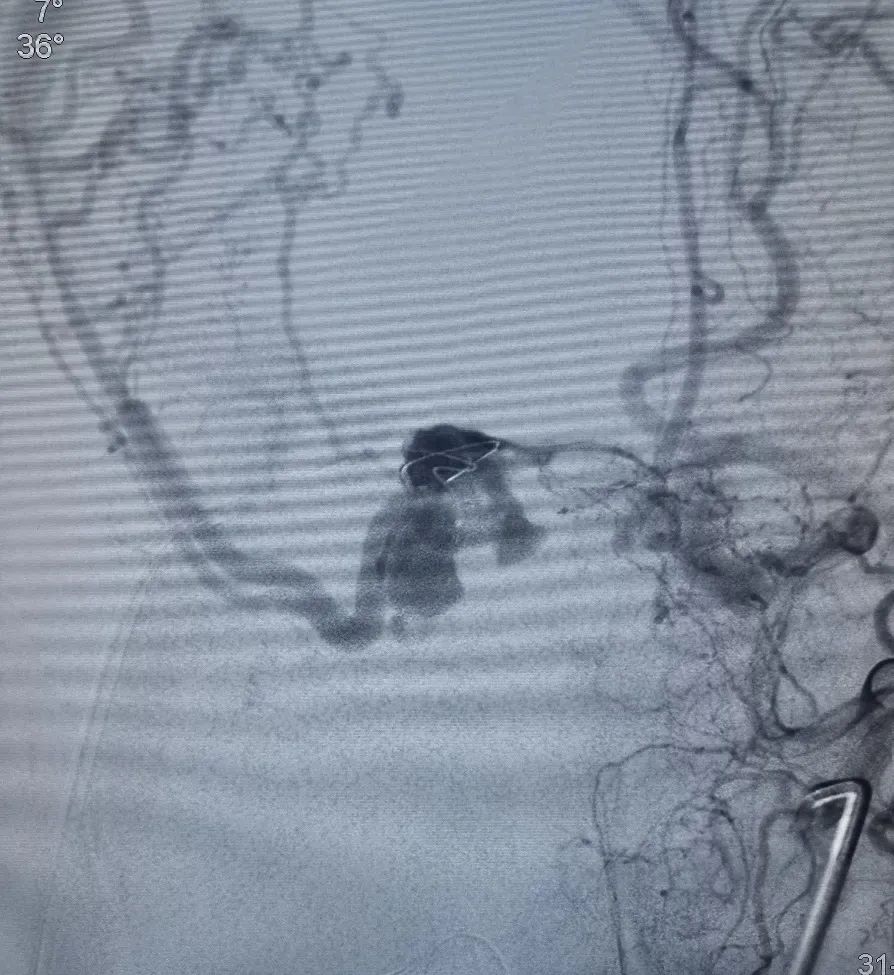

术前造影。

全麻插管成功后,常规双腹股沟、大腿根部及会阴部消毒、铺巾,穿刺右股动脉及左股静脉,均置6F鞘。全身肝素化后,泥鳅导丝携5F造影导管经右侧股动脉鞘至左颈外动脉起始部,以备术中造影。泥鳅导丝携6F Heralder® DA远端通路导管经左侧股静脉鞘至右颈内静脉,根据造影结果选择工作角度。

在Roadmap下,用泥鳅导丝开通右侧岩下窦,泥鳅导丝成功超选至右侧海绵窦内。

造影证实泥鳅导丝位置。

在Roadmap下,用0.014" 微导丝携第1根Echelon-10微导管超选通过开通的岩下窦进入海绵窦内,远端位于瘘口附近,微量造影证实微导管位置。

然后撤出泥鳅导丝,在Roadmap下,用0.014" 微导丝携第2根Echelon-10微导管超选通过开通的岩下窦进入海绵窦内,在3D造影辅助下选取工作角度,将第2根Echelon-10微导管成功超选至右侧蝶顶窦开口处,微量造影证实微导管位置。

调整第2根Echelon-10微导管位置后,先向蝶顶窦开口处填入Jasper®弹簧圈。

然后通过第1根微导管向瘘口处海绵窦注射Onyx栓塞剂。注射过程中通过造影导管在左侧颈外动脉反复造影,直至该海绵窦硬脑膜动静脉瘘完全不显影。最后做双侧颈总动脉造影,见右侧海绵窦硬脑膜动静脉瘘完全不显影,双侧颈内动脉、大脑中动脉、大脑前动脉及其它分支显影良好。行CT示颅内未见明显出血。